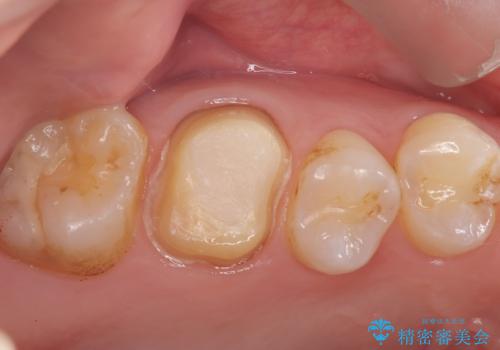

【奥歯のセラミッククラウン】他院で根管治療も必要だといわれた。

- 他院で歯の根っこの先端に膿が溜まっているため治療が必要だといわれた患者様です。

根っこの治療を顕微鏡を見ながら行ってくれる医院を探して当院に来院されました。

以前治療した際のむし歯が大きく、長い年月の間に少しずつ歯髄が死んでしまったと思われる状況でした。

長期にわたる炎症により、口蓋根尖は吸収を起こしていたため、MTAにて充填しています。